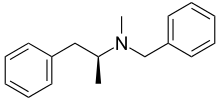

| Synonyms | N-benzyl-N-methylamphetamine |

| Formula | C17H21N |

| Molar mass | 239.355 g/mol |